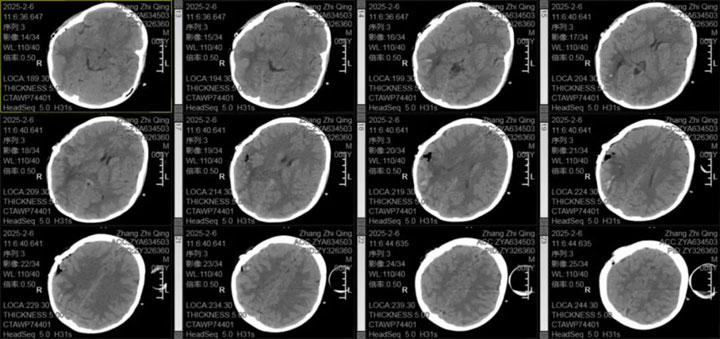

东方总院神经外科医疗中心张德辉院长和吴全主任对该患儿的病情高度重视,术前组织了详细的病例讨论,制定了周全的手术方案。由于出血部位靠近功能区,术后存在偏瘫风险;尽管CTA未发现异常,但仍不能完全排除颅内动脉瘤、脑血管畸形等病因,手术风险较高;手术将采用显微镜下精细操作,以预防可能的动脉瘤破裂或血管畸形出血,并减少手术创伤;同时,考虑到患儿年龄小,头部切口护理难度大,颅骨缺损不利于儿童身心康复,张德辉院长决定采取颅骨骨瓣回纳的方式,减少二次手术创伤。

手术过程中,医生团队凭借精湛的医术和丰富的经验,不负所托,顺利完成了手术。术后,患儿未出现神经功能障碍,结果与期待完美重合,恢复情况良好。经过一段时间的精心护理和治疗,患儿最终康复出院。